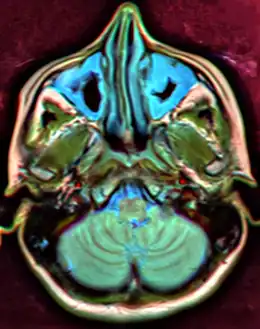

![]() | |

| A CT scan showing sinusitis of the ethmoid sinus | |

CT of chronic sinusitis

CT scan of chronic sinusitis, showing a filled right maxillary sinus with sclerotic thickened bone.

MRI image showing sinusitis. Edema and mucosal thickening appears in both maxillary sinuses.